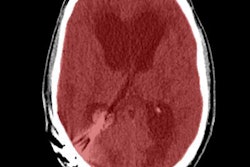

The workups confirmed that 33 of the patients had a stroke and another 27 had a TIA. CT perfusion mismatch -- that is, increased relative mean transit time (rMTT) but symmetrical regional cerebral blood volume (rCBV) -- was found in 36% of the stroke and 19% of the TIA patients; this is indicative of ischemic penumbra. In addition, 27% of the stroke patients had matched CT perfusion defects, which are represented by increased rMTT and reduced rCBV, and which point to a completed infarct.

Of the stroke and TIA subjects, 21 in each group also underwent an MRI within 24 to 48 hours of admission. The results correlated in 67% of the stroke cases and 100% of the TIA cases. In the remaining seven patients, small lacunar infarcts of multifocal small embolic infarcts were seen on MRI.